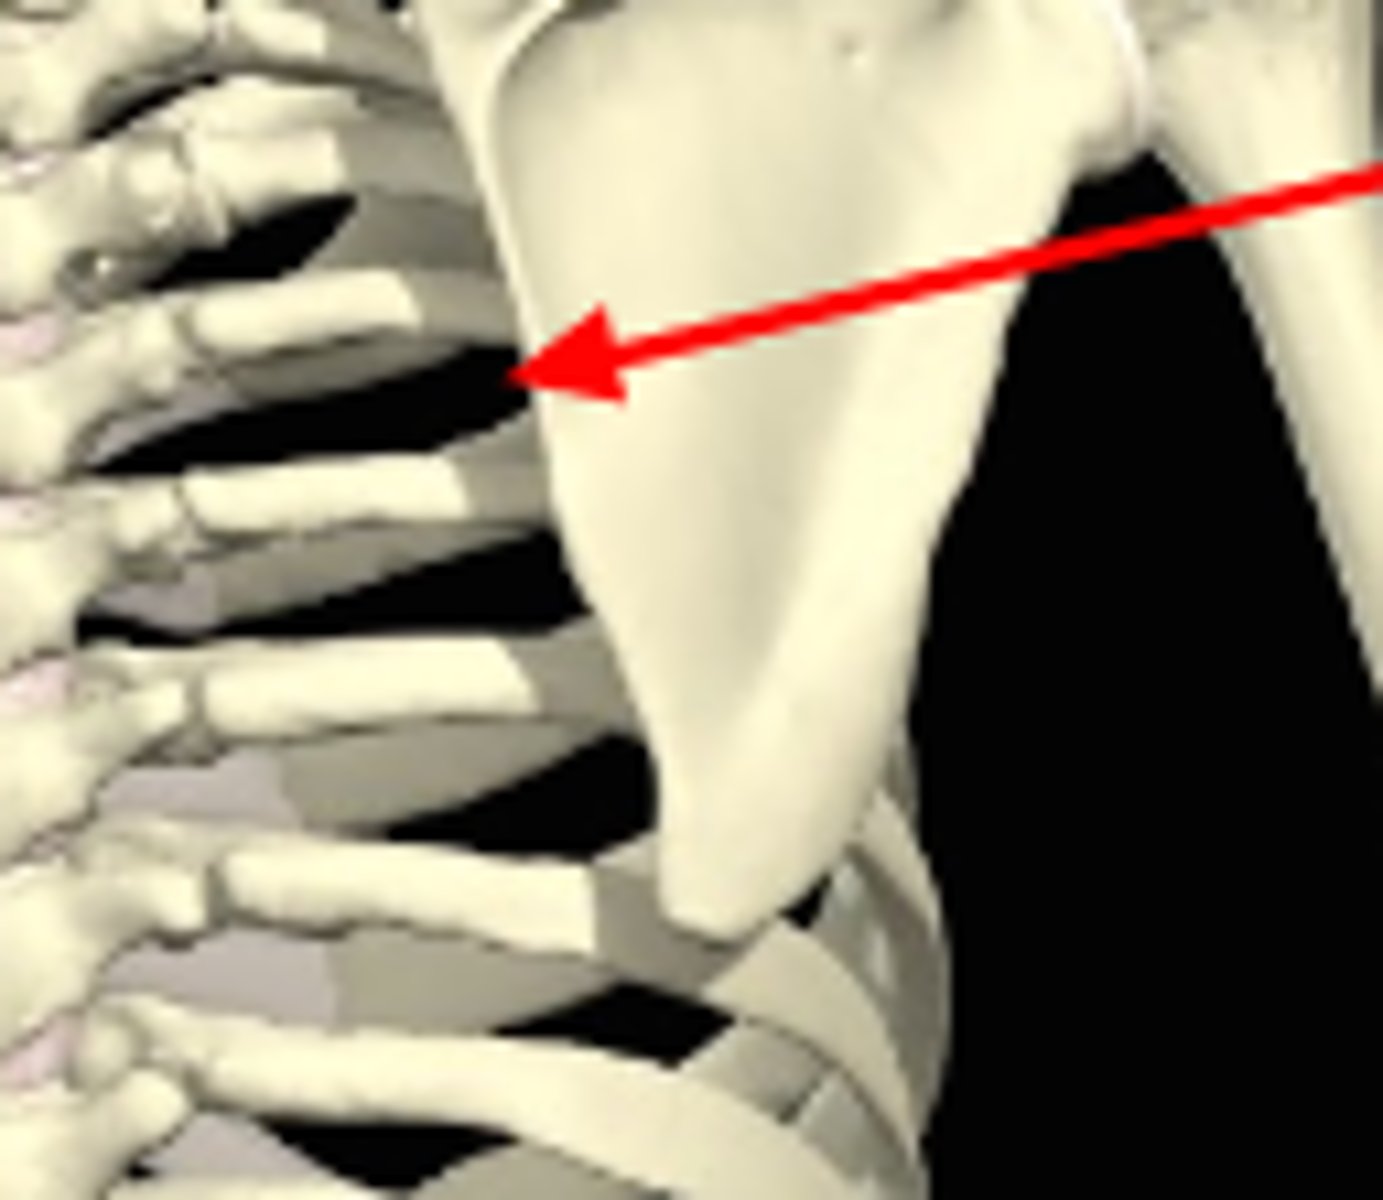

scapulothoracic j. , false joint

What joint is this? and what type of joint is it?